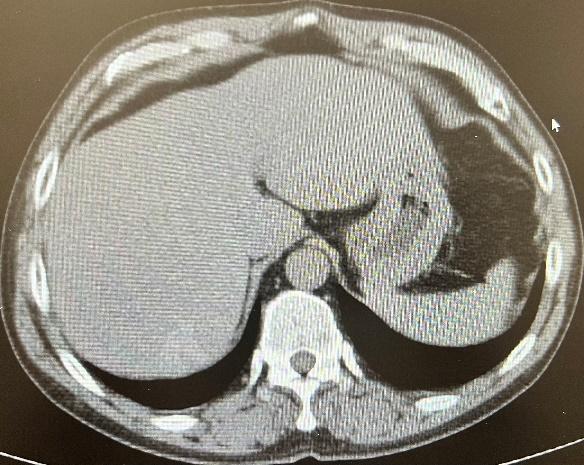

【专题综述】肝炎性假瘤的ct表现及病理分析

图片尺寸927x664

肝炎性假瘤影像学表现

图片尺寸987x746